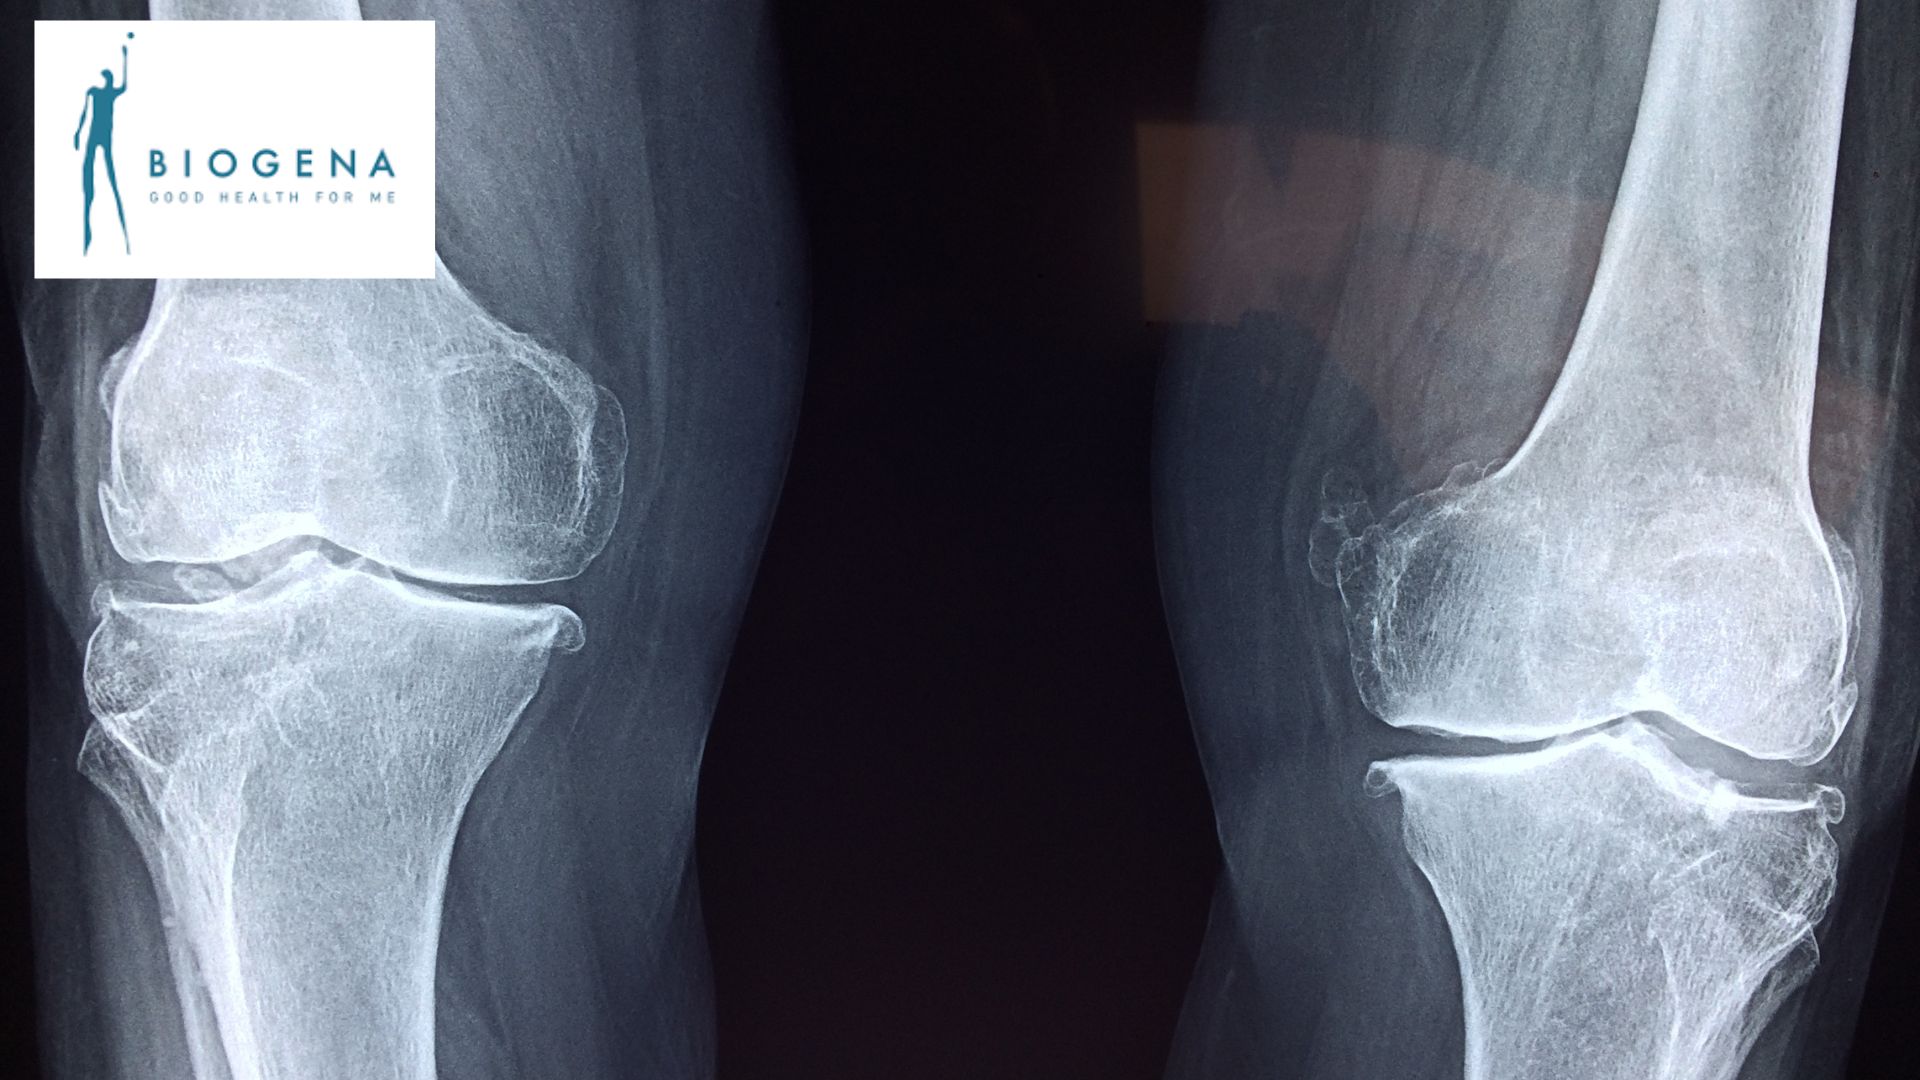

Eine professionelle Knochendichtemessung liefert wichtige Hinweise auf die Stabilität der Knochen – noch bevor Beschwerden entstehen.

Viele Frauen und auch Männer sind im Laufe ihres Lebens von Osteoporose betroffen – oft lange unbemerkt.

Die Knochendichte nimmt schleichend ab, Symptome treten meist erst dann auf, wenn bereits Schäden bestehen.